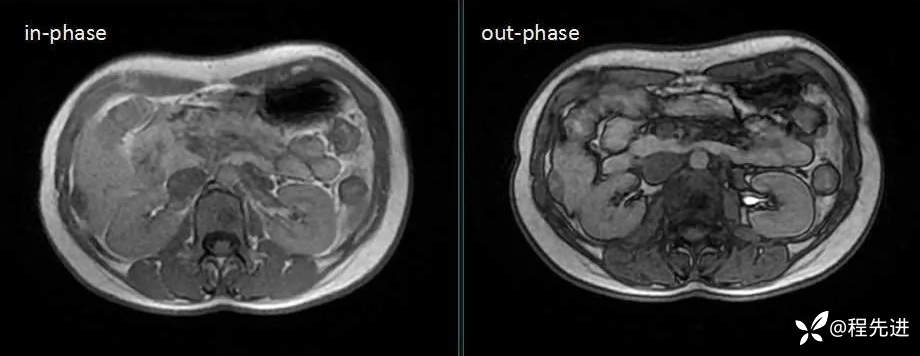

MRI检查: